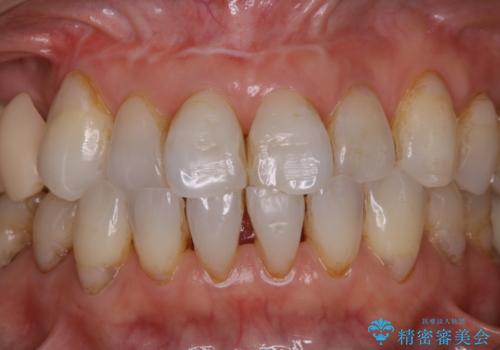

ステインが全体的についていたのでPMTCでステインを除去しオフィスホワイトニングを行いました。

ホワイトニングは薬剤を塗布し、レーザー照射を三回行いました。